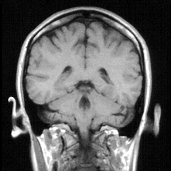

FizF0128

Koponya MR felvétele

(Szupravezető; MR-felvétel.)

ifj. Zátonyi Sándor: FIZIKA 10. (135. oldal)